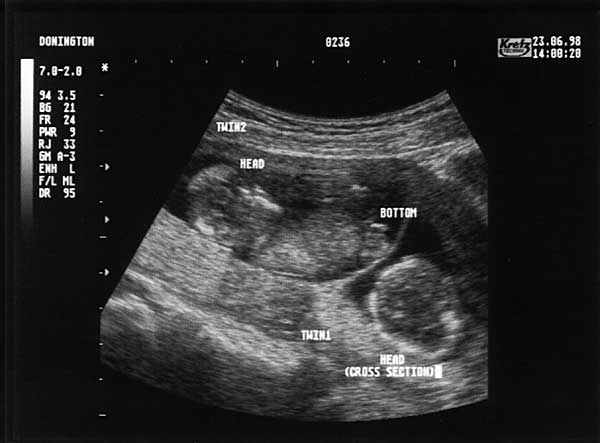

13 Weeks - Tuesday 23rd June 1998 (Approx 75mm)

Thirteen Week Scan 3

Twin 2 (Lucy) top left, lying on back, head to top left. Twin 1 (Emma) bottom right, looking down on top of head.